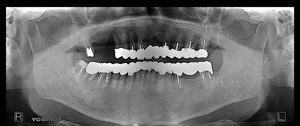

H.F‚³‚ñ @64Î —«@Žå•w@Žèp“ú  ‚Q‚O‚P‚P”N ‚PŒŽ‚Q‚P“úi‹àj   ㉺Š{ƒm[ƒxƒ‹ƒKƒCƒhŽg—p@ Ö¬“à’ÁÖ@•¹—p@

@@@@@ãŠ{@@ALL on ‚U @’x‰„‰×d@@‚h‚oƒCƒ“ƒvƒ‰ƒ“ƒg ‚T–{–„“üƒvƒƒrƒZƒbƒg

@@@  @@@@@@”16@Rp‚Œ Tapered Groovy Wp ~ 13 mm@@ @ ”14 Nb  Speedy Groovy Rp ~ 11.5 mm@@@@”12@Bmk MK‡V Rp 3.75 ~ 11.5 mm

@@@@ @@@@@ ”22@Bmk MK‡V Rp3.75  ~ 11.5 mm@@         ”24 Nb Speedy Groovy Rp  ~ 11.5 mm@@@@”2‚U Rpl  Tapered Groovy Wp  ~  13 mm@@

@@@@‰ºŠ{@@ALL on ‚U @‘¦Žž‰×d

@@@@ @@@@@ ”36 Rp‚Œ Tapered Groovy Rp ~ 10 mm  @  ”34 Rp‚Œ Tapered Rp ~ 10 mm            ”32 Rpl Tapered Np ~ 13 mm@

@@@@ @@@@@ ”42 Rp‚Œ Tapered Np ~ 13 mm@ @@ @      ”44 Bmk MK‡V Rp3.75 ~ 10 mm  @     ”4‚U Rpl Taperde Grovy Rp

~ 10 mm